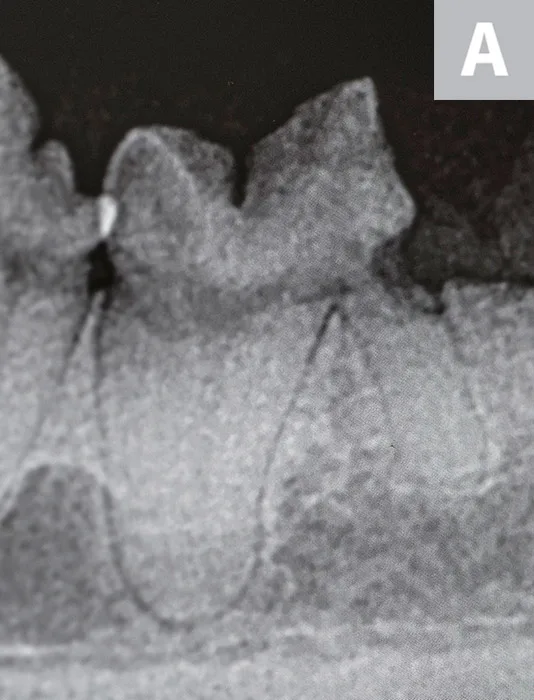

Surface resorption may occur secondary to release of osteoclast-activating factors at the site of cementum injury triggered by inflammation. Resorption can occur at any location on the root surface and progress into dentin apically and/or coronally. Surface root resorption (Figure 1) is radiographically characterized by one or more shallow voids that affect the cementum, which can extend into dentin located along the margins of the root. The periodontal ligament space and lamina dura may be locally affected.

Extracted third incisor from a cat with surface external root resorption extending to the oral cavity

When resorption stops, cells from the periodontal ligament proliferate and populate the resorbed area, depositing reparative tissue. Surface resorption is generally self-limiting unless it is exposed to the oral cavity; this is often quite painful because dentin tubules are exposed to heat, cold, and pressure.